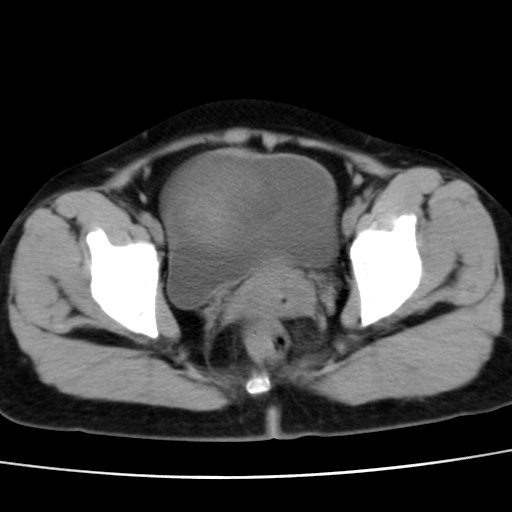

子宫多发肌瘤吗

多发性子宫肌瘤.

考虑多发子宫肌瘤,子宫直肠窝双囊性占位,另直肠周围脂肪密度增高,不知有何病史

支持考虑多发子宫肌瘤~!子宫直肠陷凹积液?

支持考虑多发子宫肌瘤~!子宫直肠陷凹积液!

子宫肌瘤,宫体部后方见液性密度影,是肠道还是子宫与直肠陷窝积液不好说,我觉得它的位置有点高

支持考虑多发子宫肌瘤!子宫直肠陷凹积液!

患者发热,而子宫直肠窝液性灶有明显边缘且局限且囊性,不除外为包裹性积液或脓肿

支持考虑多发子宫肌瘤,子宫直肠陷凹积液可能。

考虑多发子宫肌瘤

1)考虑子宫肌瘤可能性大。2)子宫后方囊性占位性病变,不排除卵巢囊肿可能。

考虑多发子宫肌瘤。子宫后方囊性占位性病变,不排除卵巢囊肿可能。